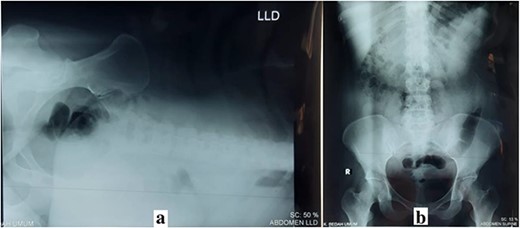

The physical examination reports the patient’s height was 155 cm and weighed 65.7 kg with a body mass index (BMI) of 27.4 (obese), a scar on the midline of the abdomen (25 cm), an enlarged abdomen (25 × 30 cm) and a change in the position of the umbilicus (Fig. 1a). Routine laboratory blood analysis results were normal. Abdominal X-rays showed an IH, and there were no obstruction signs in the intestinal (Fig. 2). RT-PCR SARS-CoV-2 result was negative.

(a) Left lateral decubitus (LLD) abdominal X-ray; (b) supine abdominal X-ray.